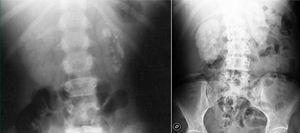

Recurrent nephrolithiasis, nephrocalcinosis, haematuria, urinary infections and rapid development of renal failure are prominent clinical manifestations. It should be highlighted that nephrocalcinosis is typical and is accompanied by nephrolithiasis or appears on its own (Figure 2).

Figure 2. Multiple renal lithiases and nephrocalcinosis in patients with primary hyperoxaluria. Simple abdominal x-ray.